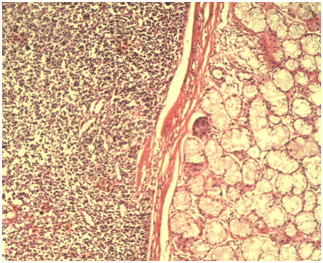

The patient was suggested to undergo tonsillectomy. Routine preoperative investigations were within normal limits and total surgical excision of the lesion through bilateral tonsillectomy was performed under general anesthesia. After completion of the tonsillectomy, both the specimens from the right and left tonsils measured approximately 3,5 cm x 2 cm x1.5 cm. Gross examination revealed a grey, irregular surfaced and 1x0,5 cm measured mass on the midline of left side tonsil (Figure 1). No other lesion was seen on the examination of the contralateral tonsil. Histopathologic examination of the left side revealed tonsilar tissue with chronic inflammation and lobules of mucous secreting salivary acini with ducts adjacent (HSG tissue) and musculary fibers to the surface squamous epithelium of the tonsilar tissue (Figures 2) (Figure 3). Histopathologic examination of the right side revealed only tonsilar tissue with chronic inflammation. A diagnosis of HSG in relation to tonsils was given. Postoperative period was uneventful and recovery was good. A year follow-up revealed no evidence of recurrence and no new relevant symptoms.

Figure 3 The heterotopic salivary gland tissue has normal structure with fibrous septae (Histopathologic examination, H&E stain, Magnifications: ×100).